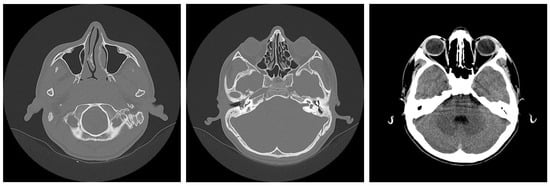

3.1.2. Computed Tomography and Magnetic Resonance Imaging

| CT Aspects | Number of Patients | Percentage |

|---|---|---|

| Fluid accumulation | 168 | 100% |

| Osteolysis | 152 | 90.47% |

| Osteocondensations | 128 | 76.19% |

| Cholesteatoma | 48 | 28.57% |

| Exocranial extensions | 48 | 28.57% |

| Intracranial extensions | 24 | 14.28% |

| Changes to the external auditory canal | 68 | 40.47% |

| Ossicular chain damage | 144 | 85.71% |